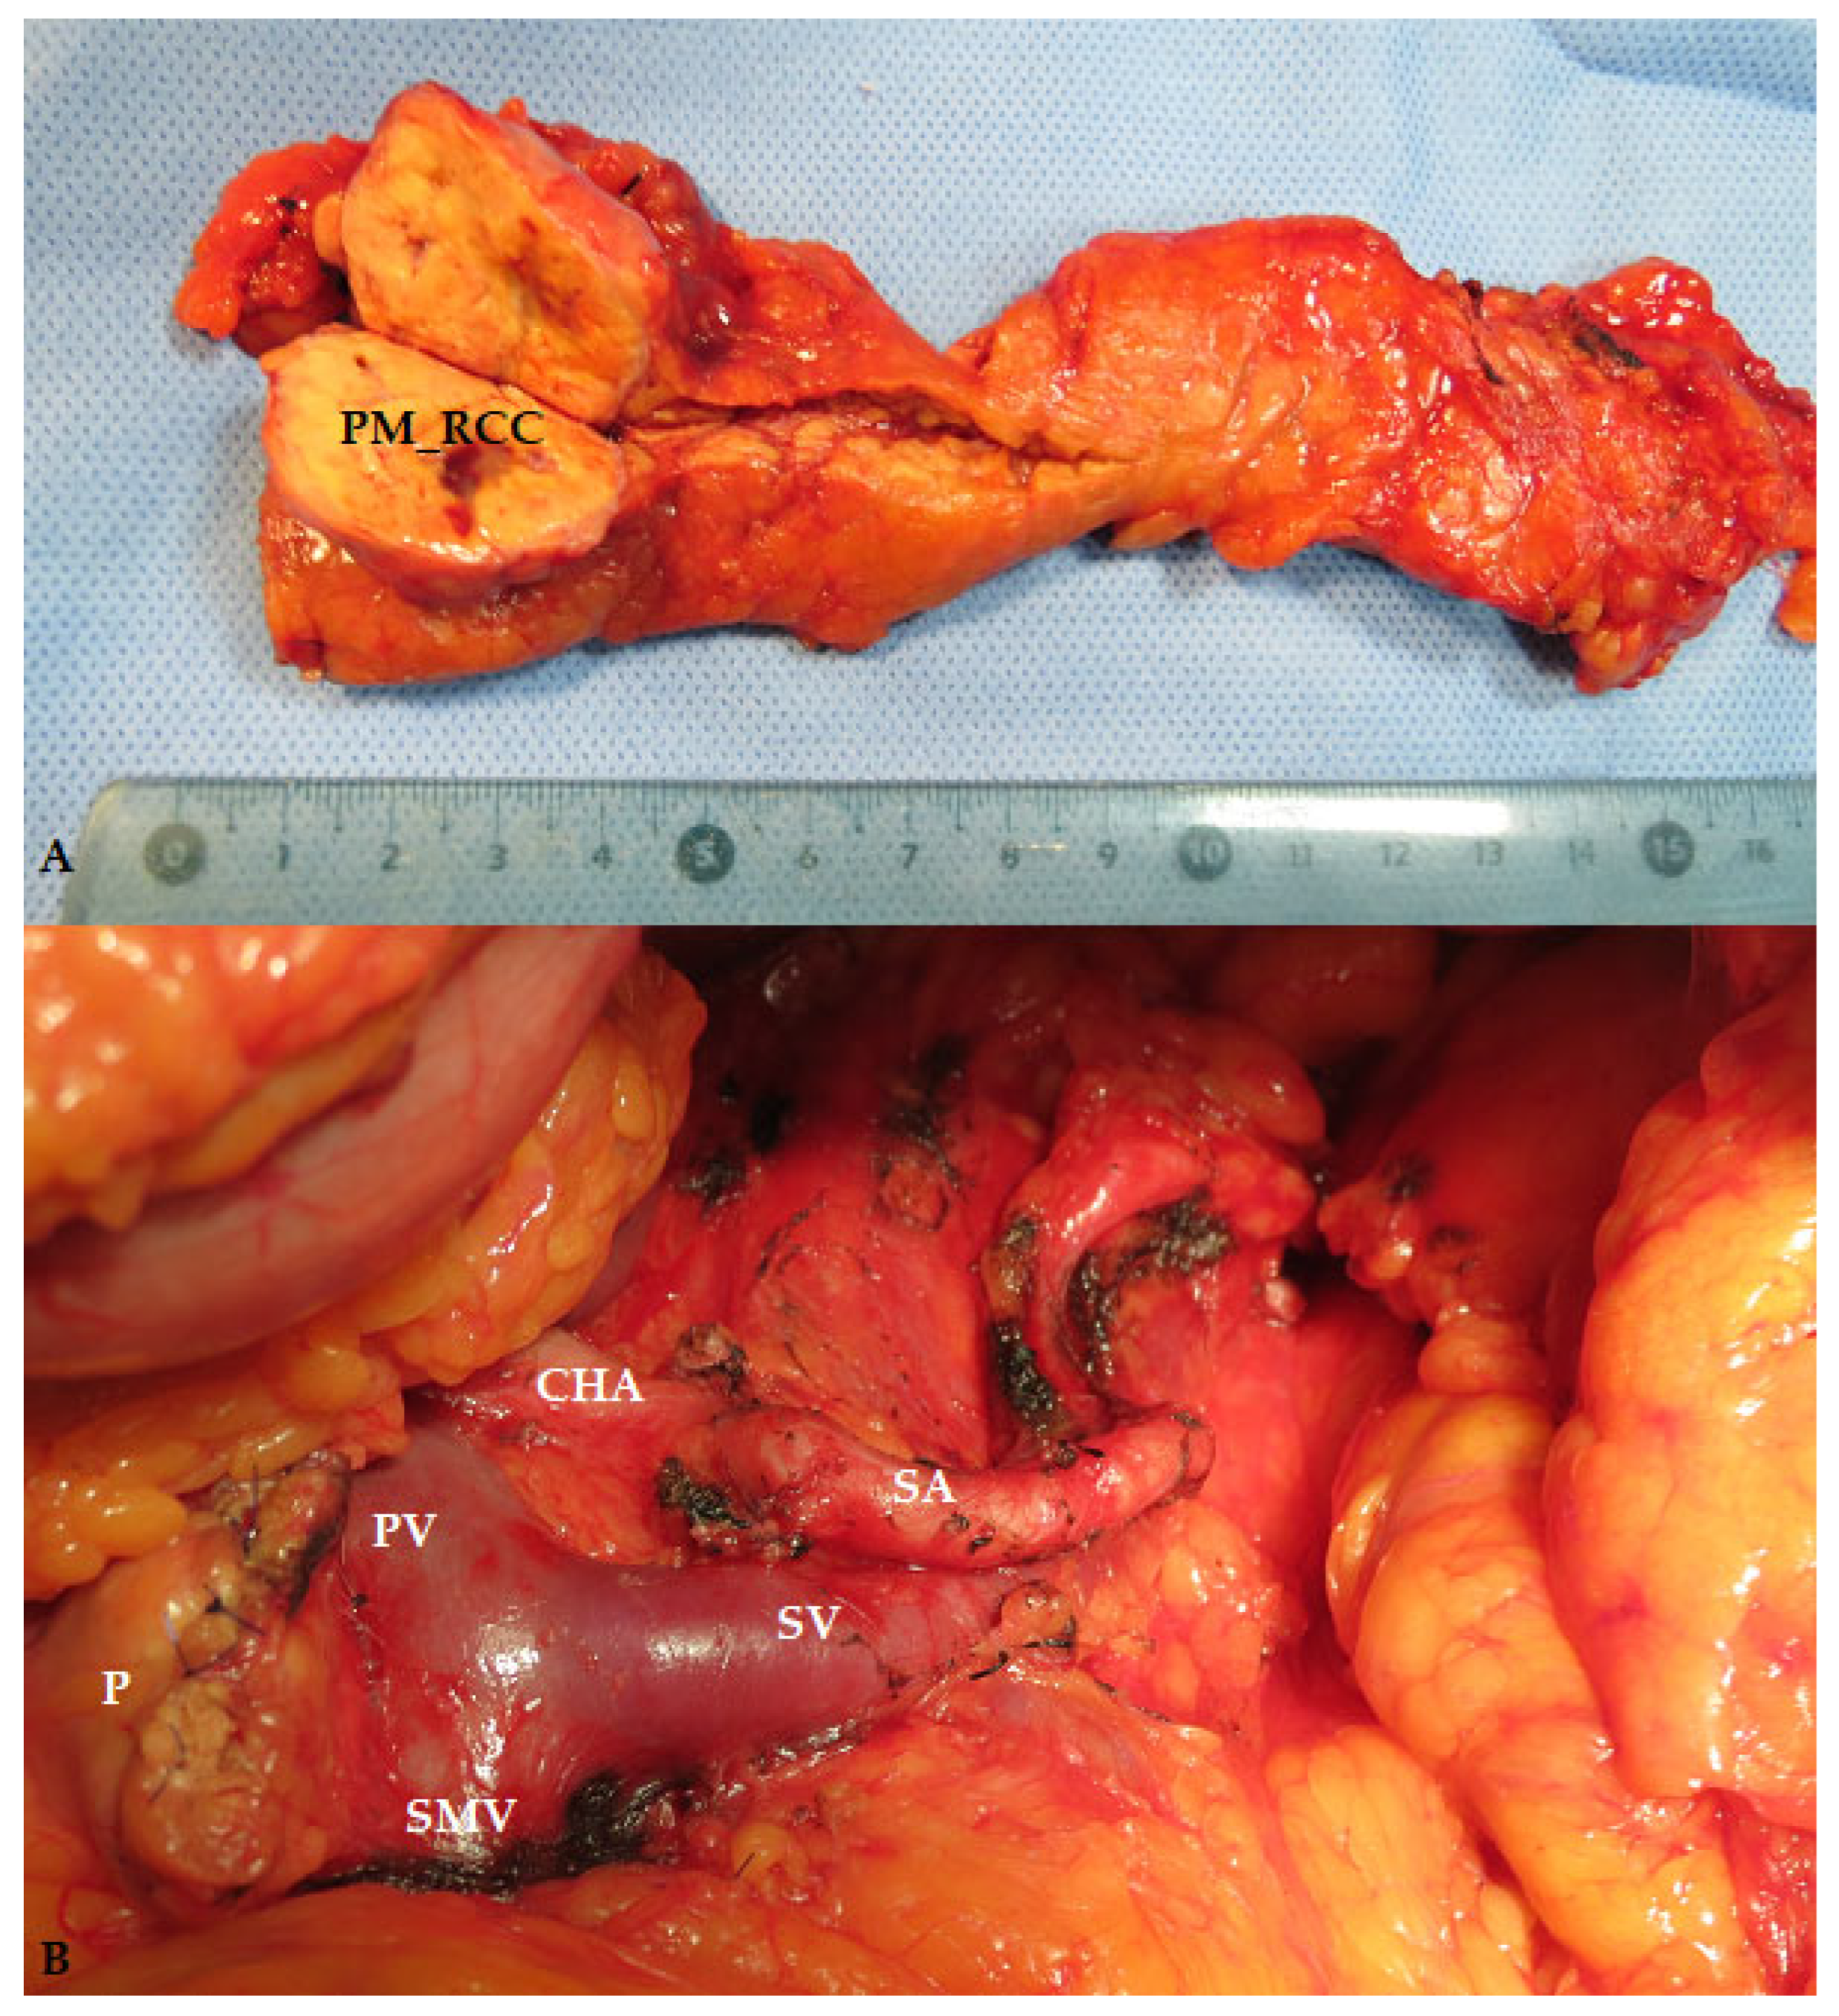

- Krisboi, I.; Breazu, C.; Pop, M.; Iancu, C.; Bartoş, A. Multiple Pancreatic Metastasis of Clear Renal Cell Carcinoma Associated with Neuroendocrine Tumor. Chirurgia 2023, 118, 317. [Google Scholar] [CrossRef] [PubMed]